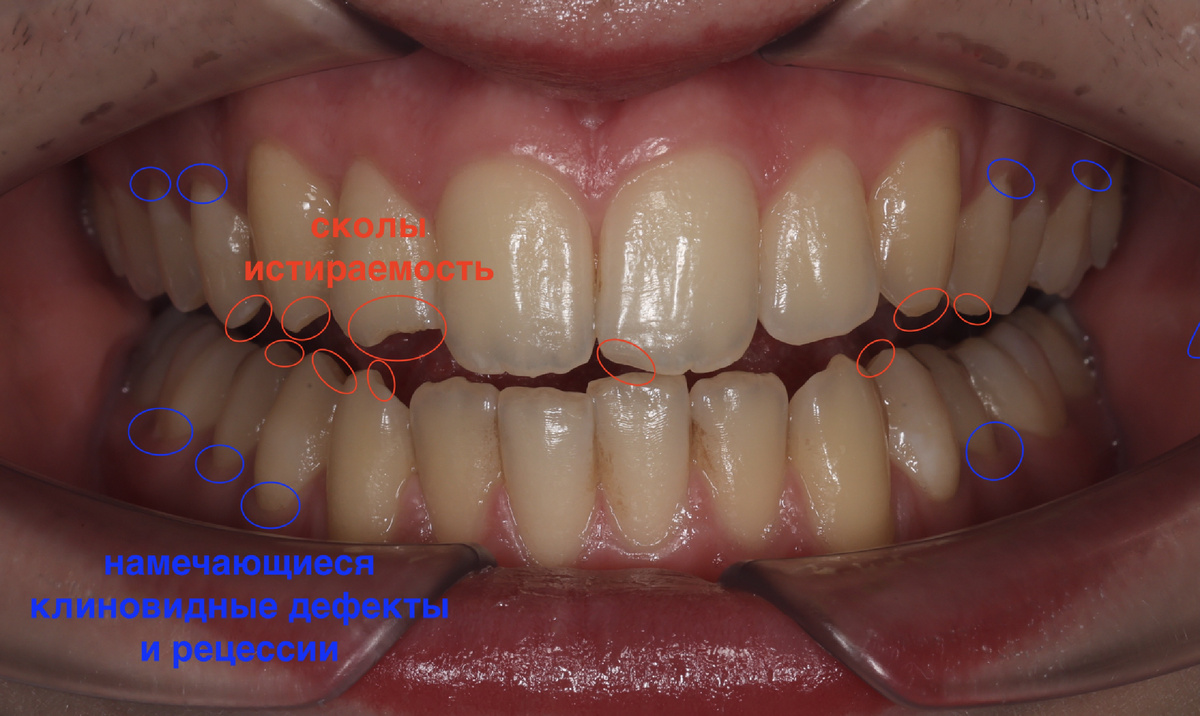

У Руслана, нашего пациента 17 лет от роду, нет каких-то визуальных дефектов. Нет кривых зубов, перекошенного лица, щелей - всё у парня прилично и с зубами, и с прикусом. Он обратился в клинику только ради эстетики.

Для 17 лет - норма. Но мы же врачи и, если приглядеться по внимательнее, то обнаружим некие "звоночки", сигнализирующие о том, что не всё так безопасно:

Уже имеются сколы и истираемость эмали, видим слабые места, где намечаются клиновидные дефекты и рецессии. Ещё ничего не случилось фатального, но в будущем приведёт к достаточно неприятным последствиям.